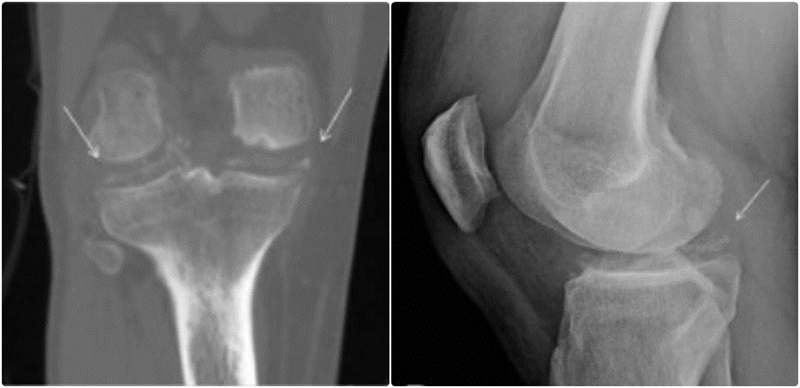

图1.受累部位呈点状、线状或斑片状钙化影(受累部位钙化所致),以及受累关节间隙间隙变窄,并可伴骨赘形成